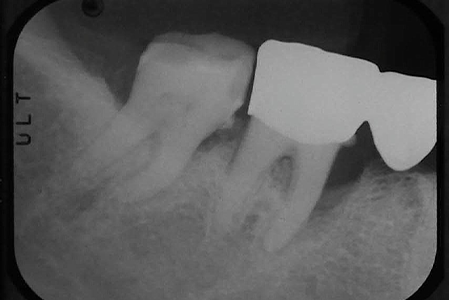

| 治療の経緯 | 口臭と歯が揺れているとのことで来院された患者様です。 歯周ポケットが10mmあり、歯茎も腫れ、このままただのクリーニングだけだと数年後には確実に抜歯になることが予想されます。 |

| 治療方法 | 再生療法を行い、骨の再生を促しました。 レントゲンを見る限り、明らかな骨の再生が見受けられます。 |